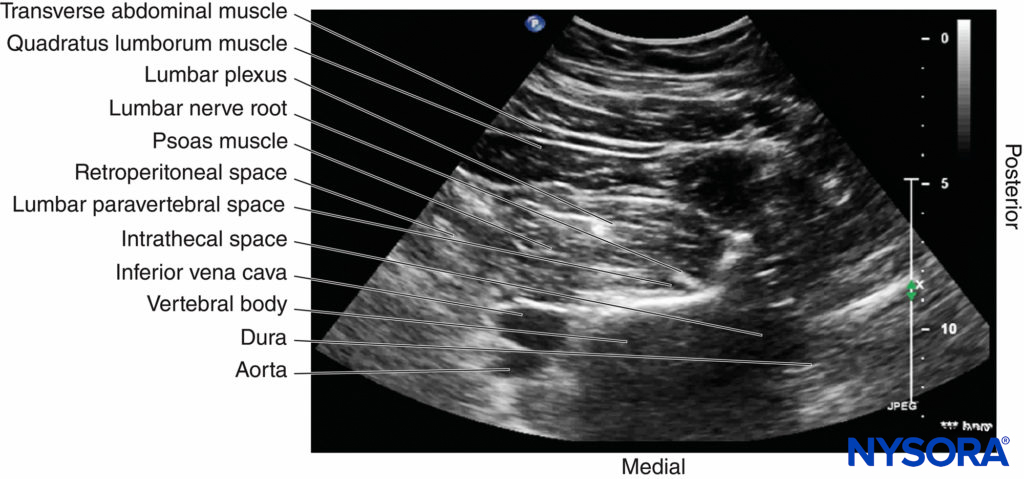

On a typical PMTOS-TP (see Figure 10b), the erector spinae muscle, transverse process, psoas major muscle, quadratus lumborum muscle, and anterolateral surface of the vertebral body are clearly visualized (see Figure 13).

The psoas muscle appears hypoechoic, but multiple areas of hyperechogenicity are also interspersed within the central part of the muscle (see Figure 13). These hyperechoic speckles represent the intramuscular tendon fibers of the psoas muscle and are more pronounced below the level of the iliac crest.

The inferior vena cava (IVC; on the right side) and the aorta (on the left side) are also identified anterior to the vertebral body (see Figure 13) and are useful landmarks to look out for while performing a PMTOS. The lower pole of the kidney, which can extend to the L3–L4 level, is closely related to the anterior surfaces of the quadratus lumborum and psoas muscles and frequently seen as an oval structure that moves synchronously with respiration in the retroperitoneal space (Figure 21). The acoustic shadow of the transverse process obscures the posterior aspect of the psoas muscle during a PMTOS-TP (see Figure 13). Therefore, the lumbar nerve root and lumbar plexus are rarely visualized through the PMTOS-TP scan window. However, the spinal canal, with the dura and the intrathecal space, may be visualized during a PMTOS-TP (see Figure 13) due to the US signal entering the spinal canal through the interlaminar space (see Figure 13). Being able to visualize the neuraxial structures during a lumbar paravertebral scan may be useful in documenting epidural spread after an LPB.

In contrast, during a PMTOS through the lumbar intertransverse space and at the level of the articular process (PMTOS-AP) (see Figure 10c), apart from the erector spinae, psoas, and quadratus lumborum muscles, the intervertebral foramen, articular process, and lumbar nerve root are clearly delineated (see Figure 14). The LPVS is also seen as a hypoechoic space adjacent to the intervertebral foramen (see Figure 14), and the lumbar nerve root can be seen exiting the foramen to enter the paravertebral space (see Figure 14).

After it exits the intervertebral foramen, the lumbar nerve root does not enter the psoas muscle directly opposite the intervertebral foramen from which it emerges (see Figure 14), but takes a steep caudal course (see Figure 14), entering the psoas muscle at the vertebral level below to join the lumbar plexus. The lumbar plexus is seen as a separate hyperechoic structure within a hypoechoic space, the psoas compartment, in the posterior aspect of the psoas muscle (see Figure 14). In a transverse sonogram produced by the shamrock method (see Figure 15), the psoas, erector spinae, and quadratus lumborum muscles are also clearly visualized (see Figures 16, 17, 18 and 19). The anatomical arrangement of the three muscles around the transverse process—that is, the psoas muscle lying anteriorly, the erector spinae muscle lying posteriorly, and the quadratus lumborum muscle lying at the apex (see Figure 16)—produces a sonographic pattern that has been likened to the shape of a “shamrock,” with the muscles representing its three leaves. The lumbar nerve root may also be visualized close to the angle between the vertebral body and the transverse process (see Figure 16) and the lumbar plexus within the posterior aspect of the psoas muscle, typically about 2 cm anterior to the transverse process (see Figures 17 and 18). From this position, if the transducer is gently tilted caudally, the acoustic shadow of the L4 transverse process disappears, and the US beam is now insonated through the intertransverse space and at the level of the articular process of the L4 vertebra, similar to that seen with a PMTOS-AP (see Figure 17). As a result, apart from the psoas, erector spinae, and quadratus lumborum muscles, the intervertebral foramen and lumbar plexus may also be visualized (see Figure 17).